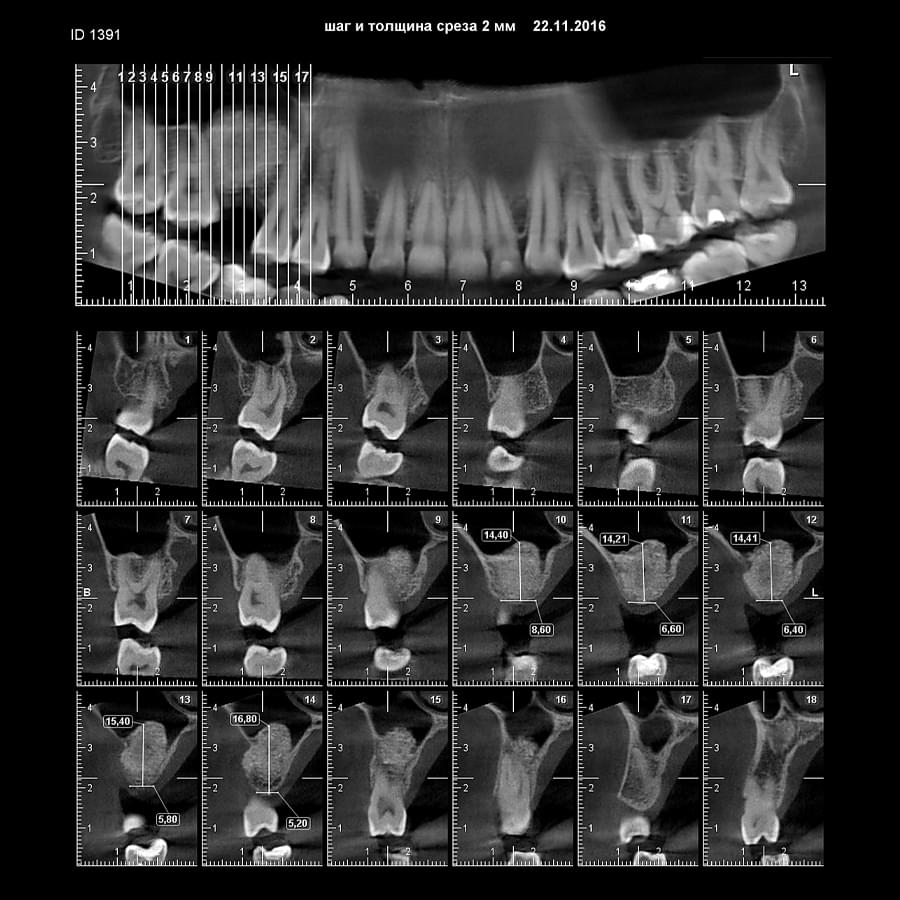

Зуб — це не просто монолітний об'єкт, а складна система мікроканалів. На плоскому 2D-знімку вони часто перекривають один одного, створюючи ілюзію простої анатомії.

Непомічений канал — це джерело майбутньої інфекції та причина «загадкового» болю після лікування. Завдяки високій роздільній здатності обладнання MyRay, лікар бачить кожен мікронний канал ще до того, як візьме до рук інструмент.

Коли коріння «ховає сюрпризи» - Корені зубів часто мають складну кривизну, гачкоподібні закручення або розгалуження, які на звичайному 2D-знімку накладаються один на одного, створюючи ілюзію прямого каналу. На плоскій картинці неможливо побачити реальний об'єм та напрямок вигину, що критично важливо при видаленні «зубів мудрості» або ендодонтичному лікуванні. КТ MyRay дає змогу лікарю заздалегідь побачити 3D-геометрію кожного кореня, оцінити його близькість до нижньощелепного нерва чи гайморової пазухи та підібрати правильну тактику роботи. Це мінімізує ризики поломки інструменту в каналі або травмування сусідніх структур, перетворюючи складну хірургію на прогнозовану процедуру.